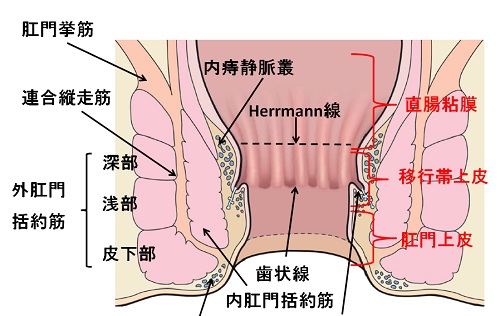

おしりの構造と病気 森外科医院 日本大腸肛門病学会認定施設 日本臨床肛門病学会認定施設 岐阜県大垣市で肛門科をお探しの方は肛門専門病院の森外科医院までご相談下さい

痔について 門田外科医院

痔ってなンだ 4 おしりだって風邪をひく

肛門外科 外科 診療科 部門紹介 外来受診される方 宇治武田病院 武田病院グループ

肛門 直腸の構造断面図イラスト 人体 医療 イメージマート

あなたの痔はどのタイプ 診療方法と肛門科診療のタイミング 内科 整形外科 肛門科 痔 浜中医院 大阪府岸和田市

肛門 断面図 直腸の写真素材

直腸と肛門管の断面は 内部の痔の位置と構造を示します Adobe Illustrator で作成されます 透明なオブジェクトが含まれています のイラスト素材 ベクタ Image

肛門に多い病気

痔 肛門 断面図 イラスト素材 フォトライブラリー Photolibrary

身体 腹部 肛門 直腸 人体解剖学 生物学 断面 の画像素材 イラスト素材ならイメージナビ

肛門 断面図のイラスト素材